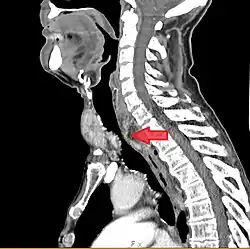

- Goitre comprimant la trachée cervicale.

Rétrécissement trachéal (flèche rouge). Tomodensitométrie (coupe transversale).

Même tumeur (coupe sagittale).